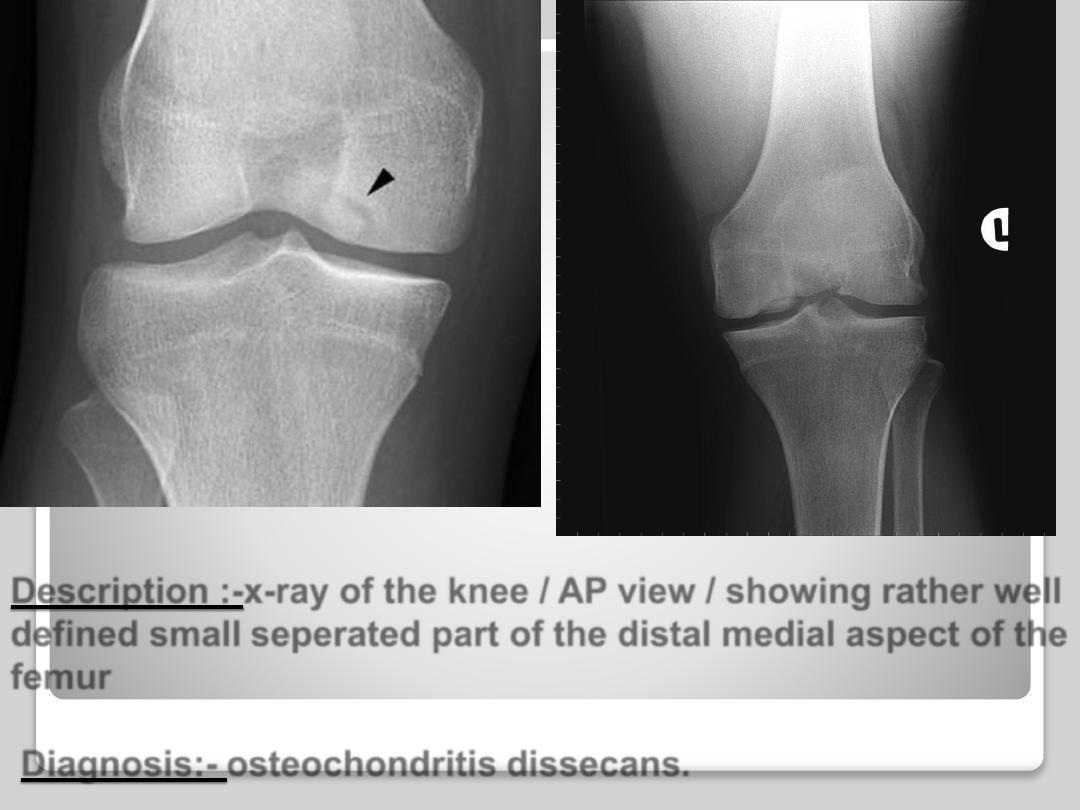

Description :-x-ray of the knee / AP view / showing rather well

defined small seperated part of the distal medial aspect of the

femur

Diagnosis:- osteochondritis dissecans.